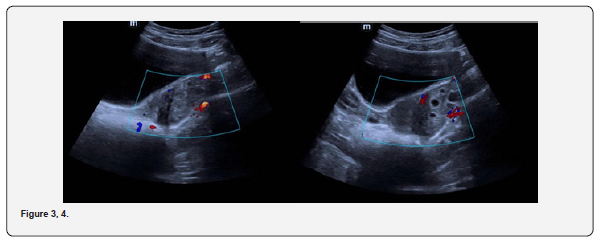

The patient is a 12-year-old girl who presented to emergency department with severe left-sided abdominal pain associated with persistent vomiting for the past two days. On physical examination left flank tenderness was noted with radiation to suprapubic area, there was no diarrhea or fever. Pelvic ultrasound with Doppler demonstrated bilaterally enlarged ovaries with small follicles with a markedly enlarged left ovary showing reduced vascularity and no evidence of identifiable ovarian cyst (Figures 1-4). Magnetic resonance imaging (MRI) demonstrated bilateral ovarian enlargement with multiple small follicles, assuming polycystic ovarian morphology. The left ovary was significantly enlarged, positioned posterior to the uterus and showed stromal edema with decreased post-contrast enhancement compared to contralateral side, findings consistent with ovarian torsion (Figures 5-10).

Common ultrasound findings include ovarian enlargement, peripheral displacement of follicles, heterogenous ovarian echotexture due to edema and reduced or absent blood flow, However, normal or preserved blood flow does not exclude ovarian torsion, particularly in cases of intermittent torsion. Previous studies have reported that the presence of Doppler flow on ultrasound cannot be used to exclude ovarian torsion whereas the absence of Doppler flow represents a significant diagnostic marker [4]. Emergency medicine literature similarly reports that Doppler flow may be present in cases of ovarian torsion and should not be used alone to exclude the diagnosis [5]. In the present case, ultrasound showed ovarian enlargement with decreased blood flow, which raised suspicion for torsion despite the absence of a clearly identifiable ovarian cyst or mass.